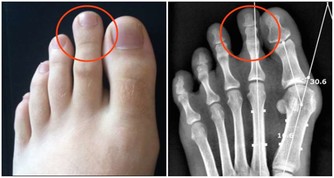

3. 你的腸道裡有寄生蟲

大便中的白色斑點也可能是絛蟲或蟯蟲。雖然如今絛蟲感染並不常見,但依然有可能。如果看到白色或黃色的斑點,可能就是絛蟲,它們通常是扁平的、方形的,大小與米粒相當。有些人可能沒有症狀,但有些人可能出現胃痛或腹瀉。人們通常是因為吃生的或未煮熟的肉而感染絛蟲。絛蟲感染比較好治療,一粒藥丸就足以殺死絛蟲,它會從糞便中排出體外。